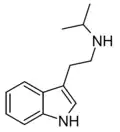

| NiPT | artificial | H | H | CH(CH3)2 | N-isopropyltryptamine | 14121-10-9 |